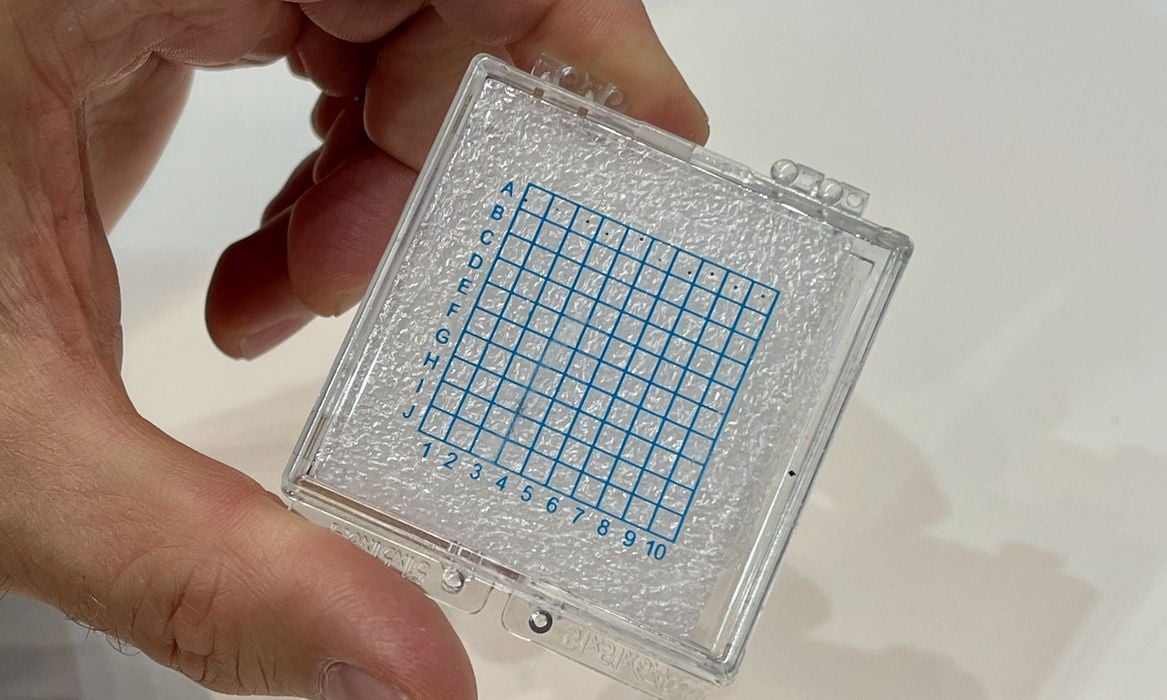

BMF Investigating Production Of 3D Printed Microneedles For COVID-19 Vaccines

BMF has been collaborating with Carnegie-Mellon University on a very promising approach to COVID-19 vaccines.